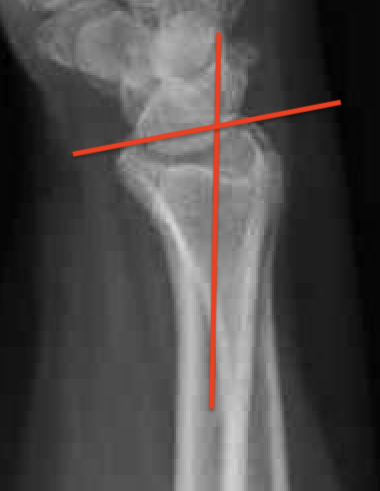

Distal Radius Angles

- radial volar tilt 11°

- radial inclination  22°

- radius is 11 mm longer than ulna

- ulna variance 2mm positive on average

Distal Radius NormalNormal Radial InclinationNormal Radial Length

4.  Radial inclination < 15o

5.  Sagittal tilt

- > 15o dorsal

- > 20o volar